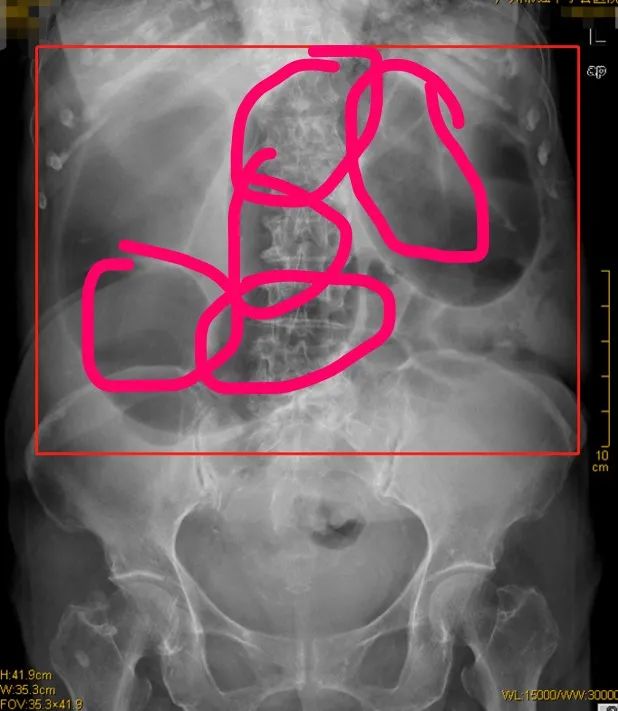

但是,假如你去胃腸外科的急診留觀室走一走,看看這些腸梗阻病人的X光平片。你會忍不住驚呼,你們胃腸外科和奧迪就是天生一對。

當腸梗阻發生,病人無法排便,腸子內的糞便不斷髮酵、產生大量積液和積氣,壓力陡然升高,讓充滿彈性的腸管擴張。

這時候,你就能看到一個腸袢和一個腸袢勾聯在一起。

這就是奧迪精神。